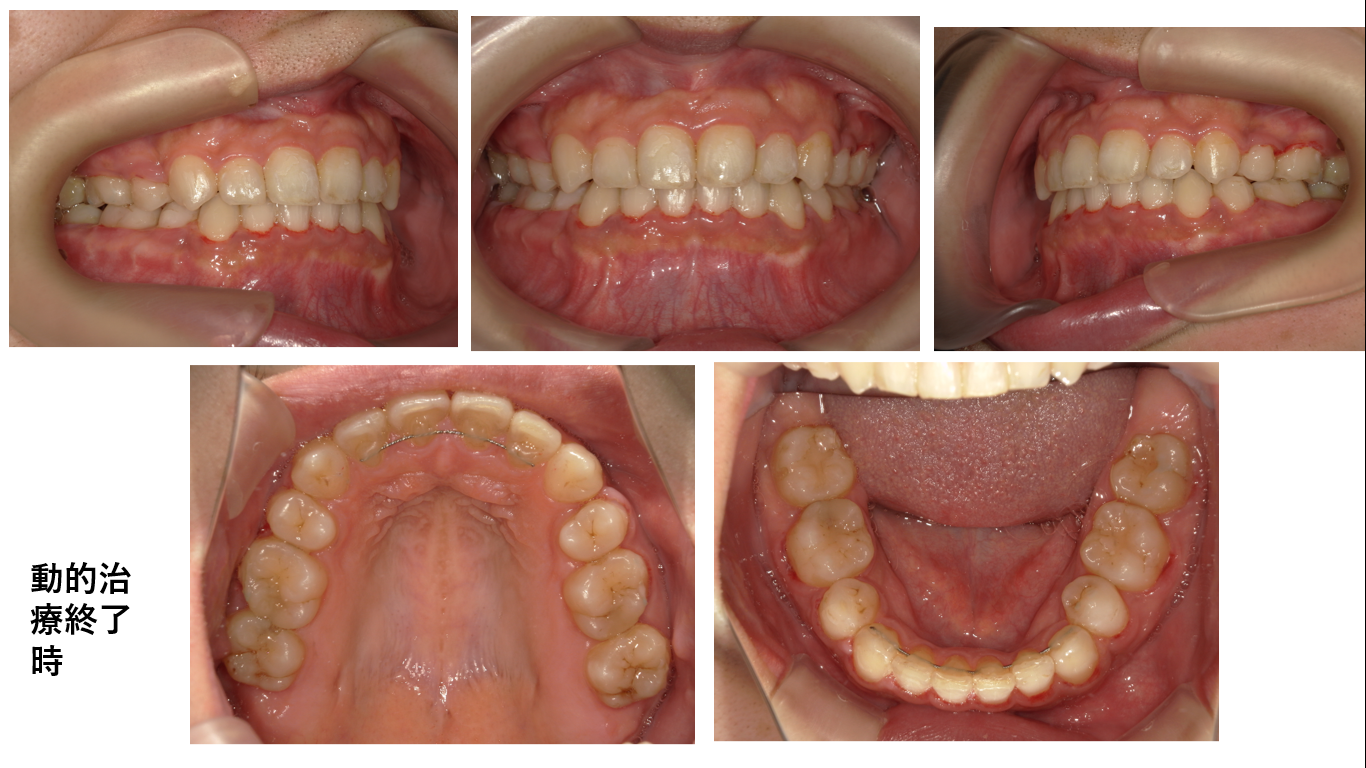

矯正症例137 AngleⅠ級叢生

治療開始年齢:32歳、抜歯部位:上下顎左右4番、治療期間3年6か月、治療費総額¥1,122,000(税込み)

この症例も抜歯が必要な症例です。このような症例にも「マウスピース矯正なら抜歯せず並びます」と言う、とんでもない歯科医師が世の中には存在しますから、矯正をお考えの方は歯科医院選びにはくれぐれも注意してくださいませ。